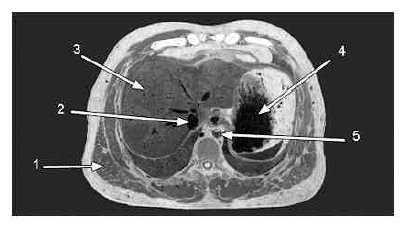

A figura acima mostra a fotografia de um corte anatômico realizado em cadáver. Considerando os dados mostrados na figura, julgue os itens a seguir.

A seta 3 indica um órgão capaz de realizar trocas gasosas.